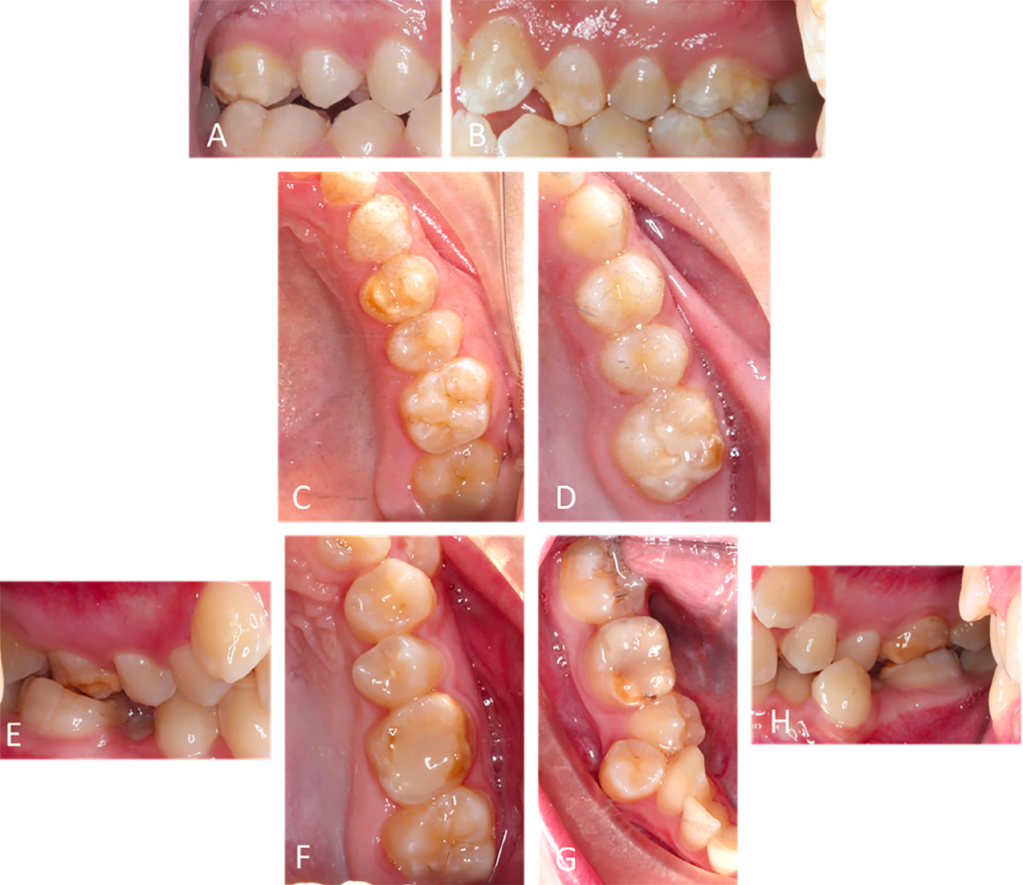

(A and B) Demarcated opacities (hypoplasia) in enamel of molars. (C and D) Opacities on the occlusal surface and posteruptive breakdown of molars. (E to H) Atypical composite restoration involving the occlusal restorations in molars.

- Demarcated opacities – The ‘Instagram filters’ of enamel defects.

- Posteruptive enamel breakdown (PEB) – The ‘oops, it’s crumbling’ stage.

- Atypical restorations – The ‘let’s fix this mess’ approach.